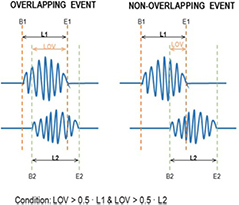

An additional factor was taken into account to discard ripples that appeared in just a few VSs and were isolated from their adjacent channels. All the detected ripples occurring at the same time segment (with a minimum of 50% of overlapping) were assigned to the same specific ripple event. The overlapping conditions are shown in figure 3. The relative power of the ripple in one virtual sensor RP(VSi) was computed as follows:

Figure 3. Schematic example of the overlapping conditions. If two events had common samples and if the length of the common samples, LOV, was higher to the half of the length of the first event L1 and the second event L2, then the both events were considered as overlapping events.

2.4. Threshold selection: precision/recall curves

Evaluation of the performance of the current algorithm was performed using iEEG signals as the gold standard. iEEG ripples were automatically detected using the time-frequency analysis algorithm described in [10]. For each pair of values considered in both thresholds (factorSD and  ) and for each automatically detected ripple in iEEG and MEG-VS, a co-occurring event was defined if these aforementioned ripples overlapped in time (see figure 3). Each ripple event in an iEEG was considered independently for each channel. In MEG-VS, all the VSs containing an overlapped event (figure 3) were considered as one individual event. This co-occurring ripple was considered a true positive (TP). An FP was defined as a detected ripple in MEG-VS that was not detected in iEEG. Finally, a false negative (FN) was defined as a detected ripple in iEEG but not visible in MEG-VS. The recall (R), precision (P) and F1 score (F1) were computed as:

) and for each automatically detected ripple in iEEG and MEG-VS, a co-occurring event was defined if these aforementioned ripples overlapped in time (see figure 3). Each ripple event in an iEEG was considered independently for each channel. In MEG-VS, all the VSs containing an overlapped event (figure 3) were considered as one individual event. This co-occurring ripple was considered a true positive (TP). An FP was defined as a detected ripple in MEG-VS that was not detected in iEEG. Finally, a false negative (FN) was defined as a detected ripple in iEEG but not visible in MEG-VS. The recall (R), precision (P) and F1 score (F1) were computed as: